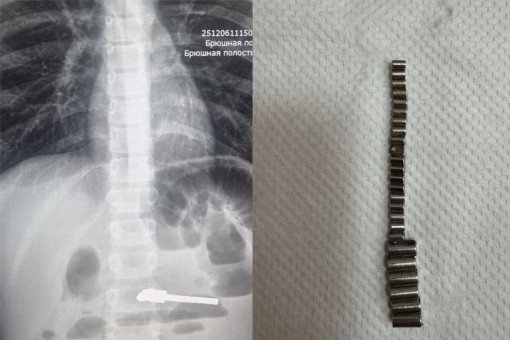

Ежегодно пациентами хирургического отделения ДГКБ № 1 становятся несколько детей, из ЖКТ которых врачи извлекают инородные тела.

25 инородных тел достали из мальчика в Новосибирске